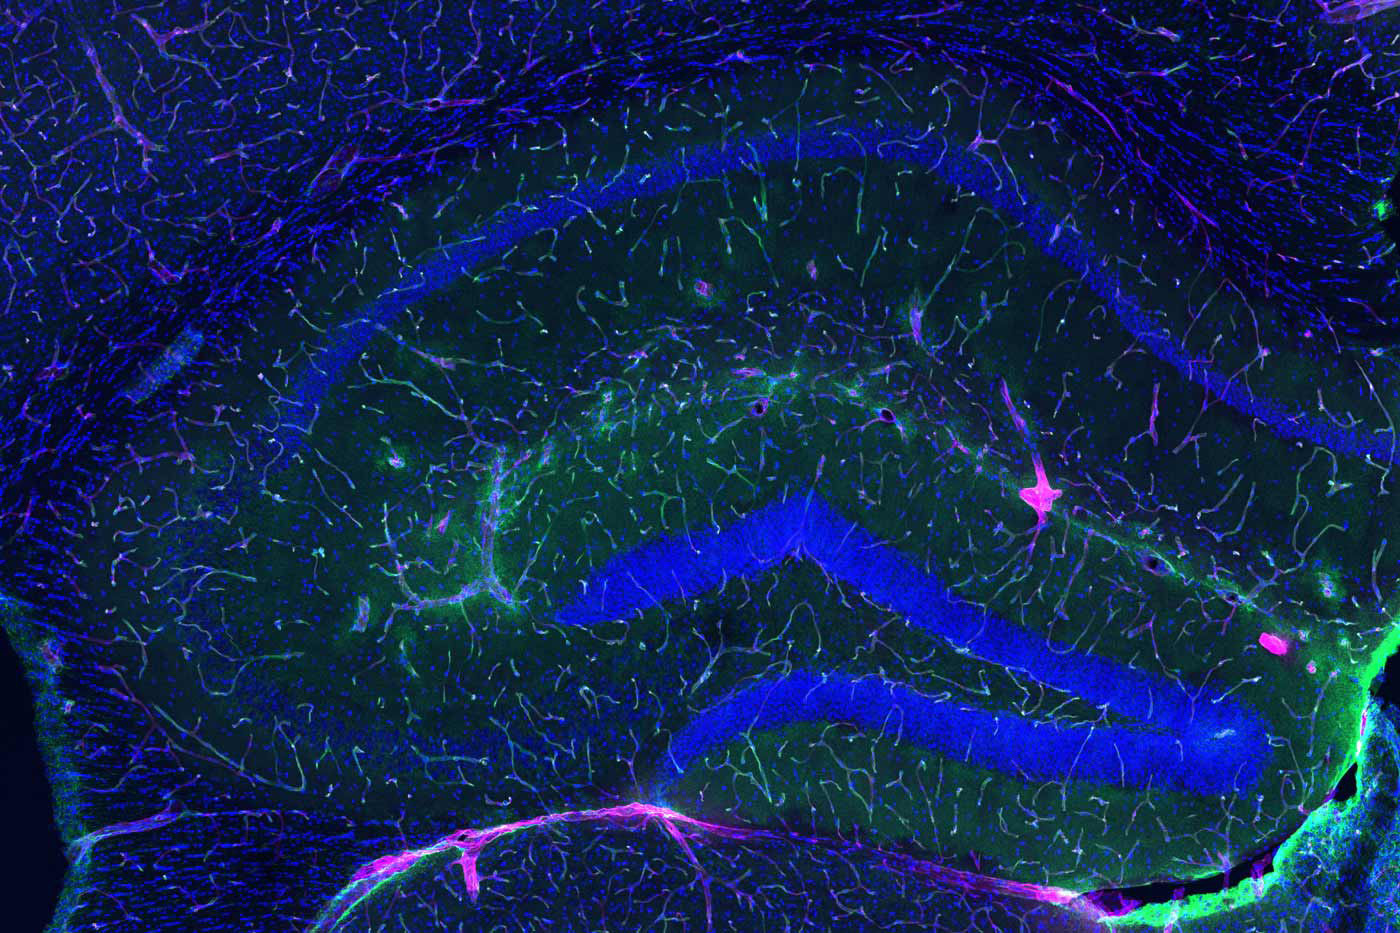

Para comprender la magnitud de este descubrimiento, debemos asomarnos a la microanatomía de la frontera cerebral. La BHE es una interfaz vascular altamente selectiva que separa el cerebro de la circulación sistémica, formada por un mosaico celular inexpugnable: células endoteliales microvasculares cerebrales (BMEC), astrocitos y pericitos.

A diferencia de otros vasos sanguíneos, las BMEC carecen de poros o fenestraciones. Están selladas por uniones estrechas (compuestas por proteínas como claudinas y ocludinas), que restringen severamente el paso de sustancias, permitiendo solo la entrada de nutrientes esenciales y orquestando la expulsión meticulosa de neurotoxinas como el amiloide-beta.

Para medir la magnitud de esta degradación en el laboratorio, los científicos no observan murallas de piedra, sino el flujo de marcadores microscópicos. Evalúan la velocidad exacta a la que fluidos y moléculas, como si fueran invasores cruzando un foso, logran traspasar el endotelio celular. Lo que en la juventud era un sello biológico hermético y casi inexpugnable, con la senescencia se convierte en un tamiz permisivo. A través de estas brechas estructurales, las células inmunitarias periféricas y las citoquinas inflamatorias logran penetrar en el cerebro.

Esta infiltración desata una tormenta de neuroinflamación crónica que hiperactiva la microglía y altera el delicado ecosistema en el que habitan las neuronas, aquellas a las que Cajal bautizó poéticamente como “las misteriosas mariposas del alma”. Este asedio inflamatorio acelera la acumulación de proteínas patológicas, precipitando la ruina cognitiva característica de enfermedades como el Alzheimer y el Parkinson.